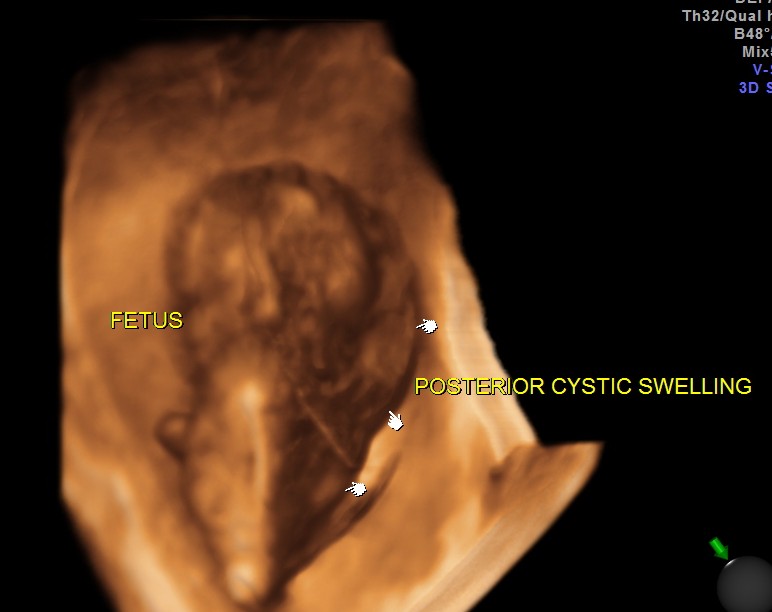

The following is 3D multi dimensional picture.

The diagnosis offered was cystic hygroma .

Cystic hygroma colli probably represent the most common cause for a neck mass detected prenatally. Other neck masses detectable ultrasonically include cervical meningomyelocele, hemangioma, teratoma, goiter, sarcoma, and metastatic adenopathy. Occasionally, a large cephalocele may mimic a neck mass. In most of these rare cases, polyhydramnios, hydrops fetalis, or other clinical features signal a careful search of the fetal neck.

* most bilateral posterior masses are cystic hygroma colli, especially multicystic masses with a midline septation.